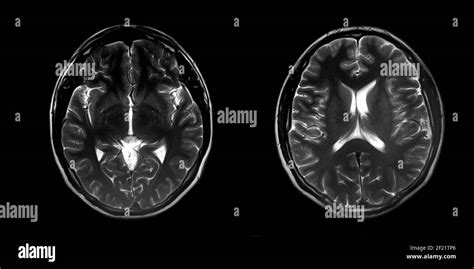

Nella NF2 e nella schwannomatosi, il follow-up è basato sulla risonanza magnetica con mezzo di contrasto effettuata periodicamente. Questo monitoraggio è cruciale per identificare precocemente la crescita dei tumori, in particolare gli schwannomi e i meningiomi. L’intervento chirurgico dei tumori cerebrali e midollari è molto rischioso, a causa della loro localizzazione in aree sensibili del sistema nervoso. Per questo motivo, si decide per l’asportazione solo in caso di crescita eccessiva o di importanti deficit neurologici in atto che compromettono la funzione o la qualità di vita del paziente. È importante notare che nei bambini e adolescenti non è indicata la radioterapia per il rischio di induzione di nuovi tumori, il che limita le opzioni terapeutiche in questa fascia d'età. Tuttavia, il farmaco bevacizumab per via endovenosa è usato per cercare di frenare lo sviluppo di schwannomi in rapida crescita, offrendo una speranza per la stabilizzazione della malattia in alcuni pazienti.